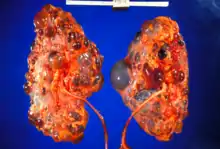

This tissue cross-section demonstrates the gross pathology of polycystic kidneys.

Renal pathology is a subspecialty of anatomic pathology that deals with the diagnosis and characterization of disease of the kidneys. In a medical setting, renal pathologists work closely with nephrologists and transplant surgeons, who typically obtain diagnostic specimens via percutaneous renal biopsy. The renal pathologist must synthesize findings from traditional microscope histology, electron microscopy, and immunofluorescence to obtain a definitive diagnosis. Medical renal diseases may affect the glomerulus, the tubules and interstitium, the vessels, or a combination of these compartments.